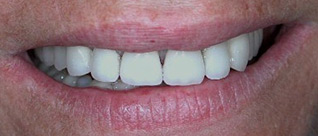

Les dents sont remplacées par des couronnes individuelles sur implants. Sourire final.